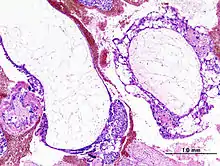

Histopathologic image of hydatidiform mole (complete type). H&E stain. | |

Based on morphology, hydatidiform moles can be divided into two types: in complete moles, all the chorionic villi are vesicular, and no sign of embryonic or fetal development is present. In partial moles some villi are vesicular, whereas others appear more normal, and embryonic/fetal development may be seen but the fetus is always malformed and is never viable.